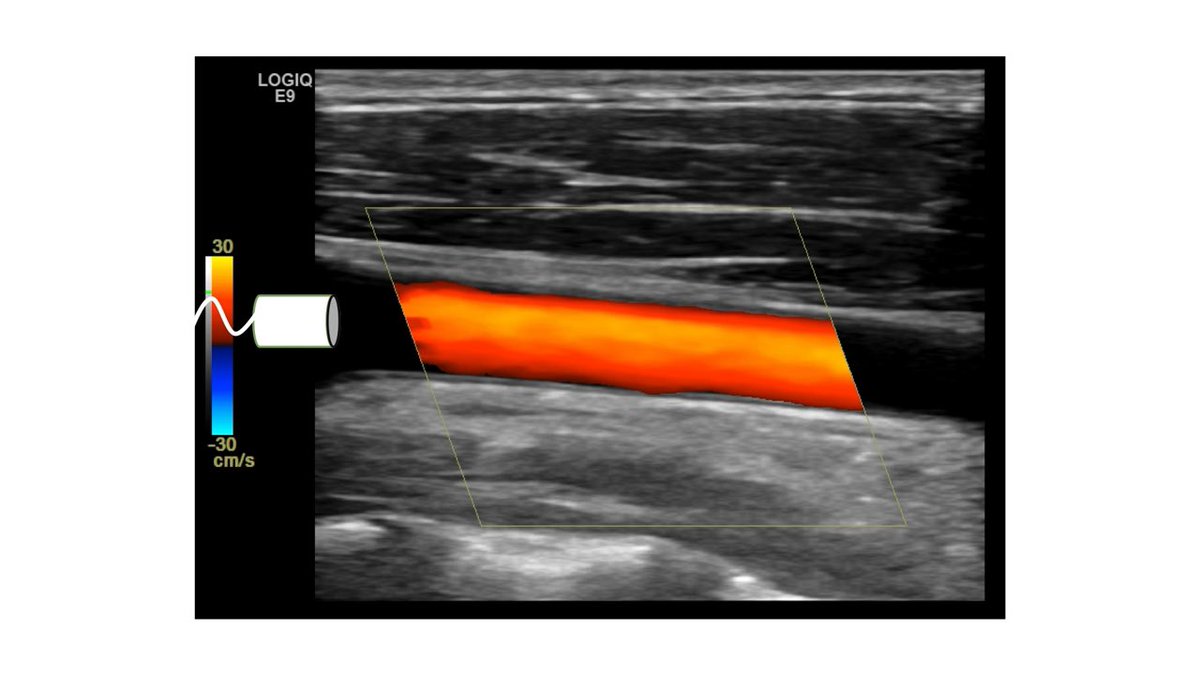

2- color map :

وهنا يهمنا الموجب أو السالب بس بغض النظر عن اللون سواء كان " ازرق او اصفر او احمر او فسفوري او اخضر مايهم لو تخيلت انهم صور حتى "

الموجب ( + ) = يدل على ان التدفق يركض للبروب

السالب ( - ) = يدل على ان التدفق هاج "يهرب" من البروب

حتى لو غيرنا وعكسنا السالب والموجب خلينا واحد تحت والثاني فوق والعكس

" مايهم مدام المبدأ ثابت "

طبق المعايير الي فوق على هالصورتين وبتعرف هل الاتجاه صحيح او لا